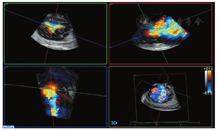

患者男,87岁,心房颤动10余年,近1年胸闷、憋喘、伴下肢水肿,不能平卧。术前经胸超声心动图(TTE)及经食管超声心动图(TEE)示:①下腔静脉宽19 mm(无呼吸塌陷率)、双房及右室增大伴轻度二尖瓣反流及极重度三尖瓣反流(tricuspid regurgitation,TR);②轻度主动脉瓣反流;③中度肺动脉高压(57 mmHg)(1 mmHg=0.133 kPa);④左室收缩功能未见异常(LVEF:63%)(图1,图2)。心电图示:心房颤动,频发室性期前收缩,ST-T改变;胸部X线示:双肺渗出,肺气肿、肺大泡,右侧胸水。CT示:三尖瓣瓣环扩大(直径:58.2 mm),右房增大(最长径:92.4 mm),下腔静脉开口增宽。临床诊断:①极重度三尖瓣关闭不全,NYHA心功能Ⅲ级;②心房颤动。鉴于该患者年龄较大以及肺气肿合并肺大泡,外科手术高危(STS评分8分,EuroscoreⅡ评分7分)症状性极重度TR,介入医生决定行经导管三尖瓣修复术。

该例患者为继发于心房颤动的FTR,三尖瓣瓣环显著扩及减少TR的作用,2D、3DTEE在评估FTR患者瓣环形态、大小、反流颈形态部位以及K-Clip™术中引导和评价中具有重要作用。